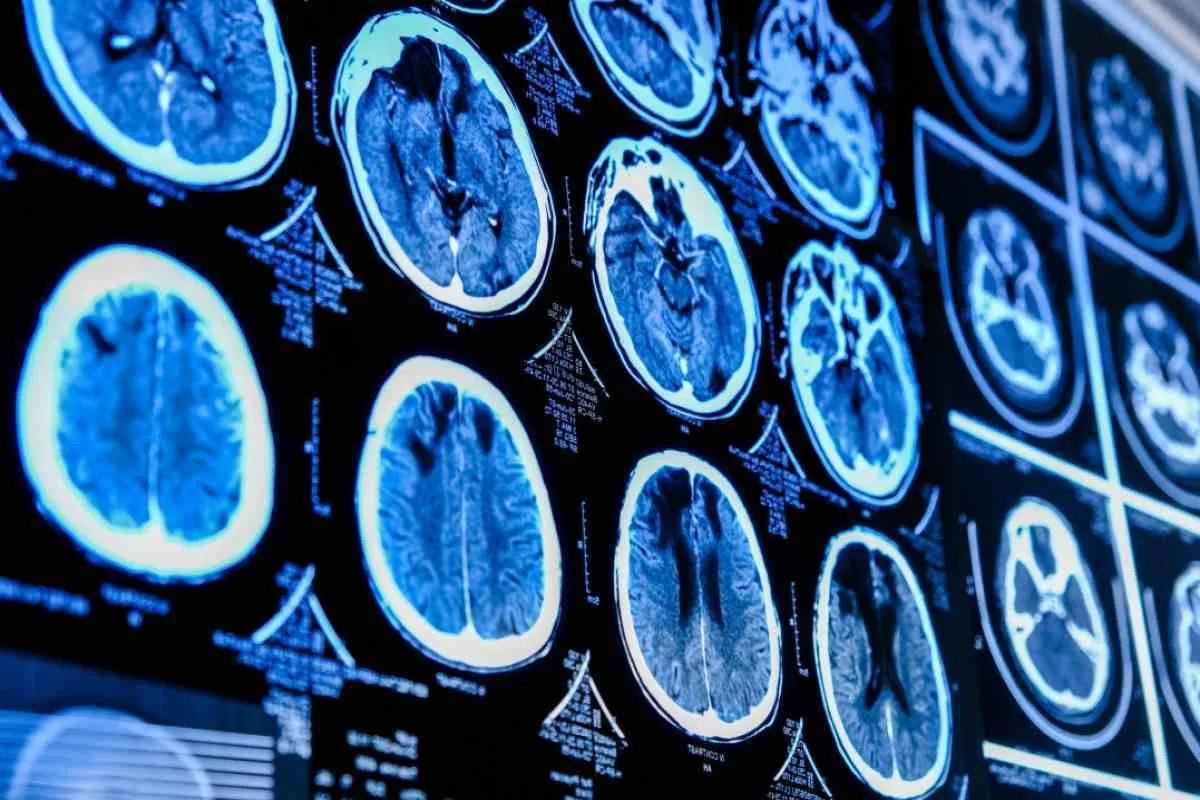

سکته مغزی

زنان بین سنین ۵۵ تا ۷۵ سال بیشتر در معرض خطر سکته مغزی هستند و به‌طور کلی، تعداد بیشتری از زنان نسبت به مردان بر اثر سکته مغزی جان خود را از دست می‌دهند.

علائم سکته مغزی نیز میان دو جنس متفاوت است، به طوری که زنان کمتر علائم معمول مانند بی‌حسی و درد را تجربه می‌کنند. به همین دلیل، بیشتر احتمال دارد که سکته مغزی در زنان به‌درستی تشخیص داده نشود.

آلزایمر

زنان، بیشتر از مردان از بیماری آلزایمر رنج می‌برند. اما باید به این موضوع توجه داشت که به طور متوسط زنان بیشتر از مردان عمر می‌کنند و سن، بزرگ‌ترین عامل خطر در مورد ابتلا به بیماری آلزایمر است.

برخی محققان دریافته‌اند که بیماری آلزایمر می‌تواند یک اختلال خودایمنی باشد که در زنان شایع‌تر است.